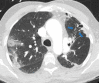

The coronavirus disease 2019 (COVID-19) pandemic is a global health care emergency. Although reverse-transcription polymerase chain reaction testing is the reference standard method to identify patients with COVID-19 infection, chest radiography and CT play a vital role in the detection and management of these patients. Prediction models for COVID-19 imaging are rapidly being developed to support medical decision making. However, inadequate availability of a diverse annotated data set has limited the performance and generalizability of existing models. To address this unmet need, the RSNA and Society of Thoracic Radiology collaborated to develop the RSNA International COVID-19 Open Radiology Database (RICORD). This database is the first multi-institutional, multinational, expert-annotated COVID-19 imaging data set. It is made freely available to the machine learning community as a research and educational resource for COVID-19 chest imaging. Pixel-level volumetric segmentation with clinical annotations was performed by thoracic radiology subspecialists for all COVID-19-positive thoracic CT scans. The labeling schema was coordinated with other international consensus panels and COVID-19 data annotation efforts, the European Society of Medical Imaging Informatics, the American College of Radiology, and the American Association of Physicists in Medicine. Study-level COVID-19 classification labels for chest radiographs were annotated by three radiologists, with majority vote adjudication by board-certified radiologists. RICORD consists of 240 thoracic CT scans and 1000 chest radiographs contributed from four international sites. It is anticipated that RICORD will ideally lead to prediction models that can demonstrate sustained performance across populations and health care systems.